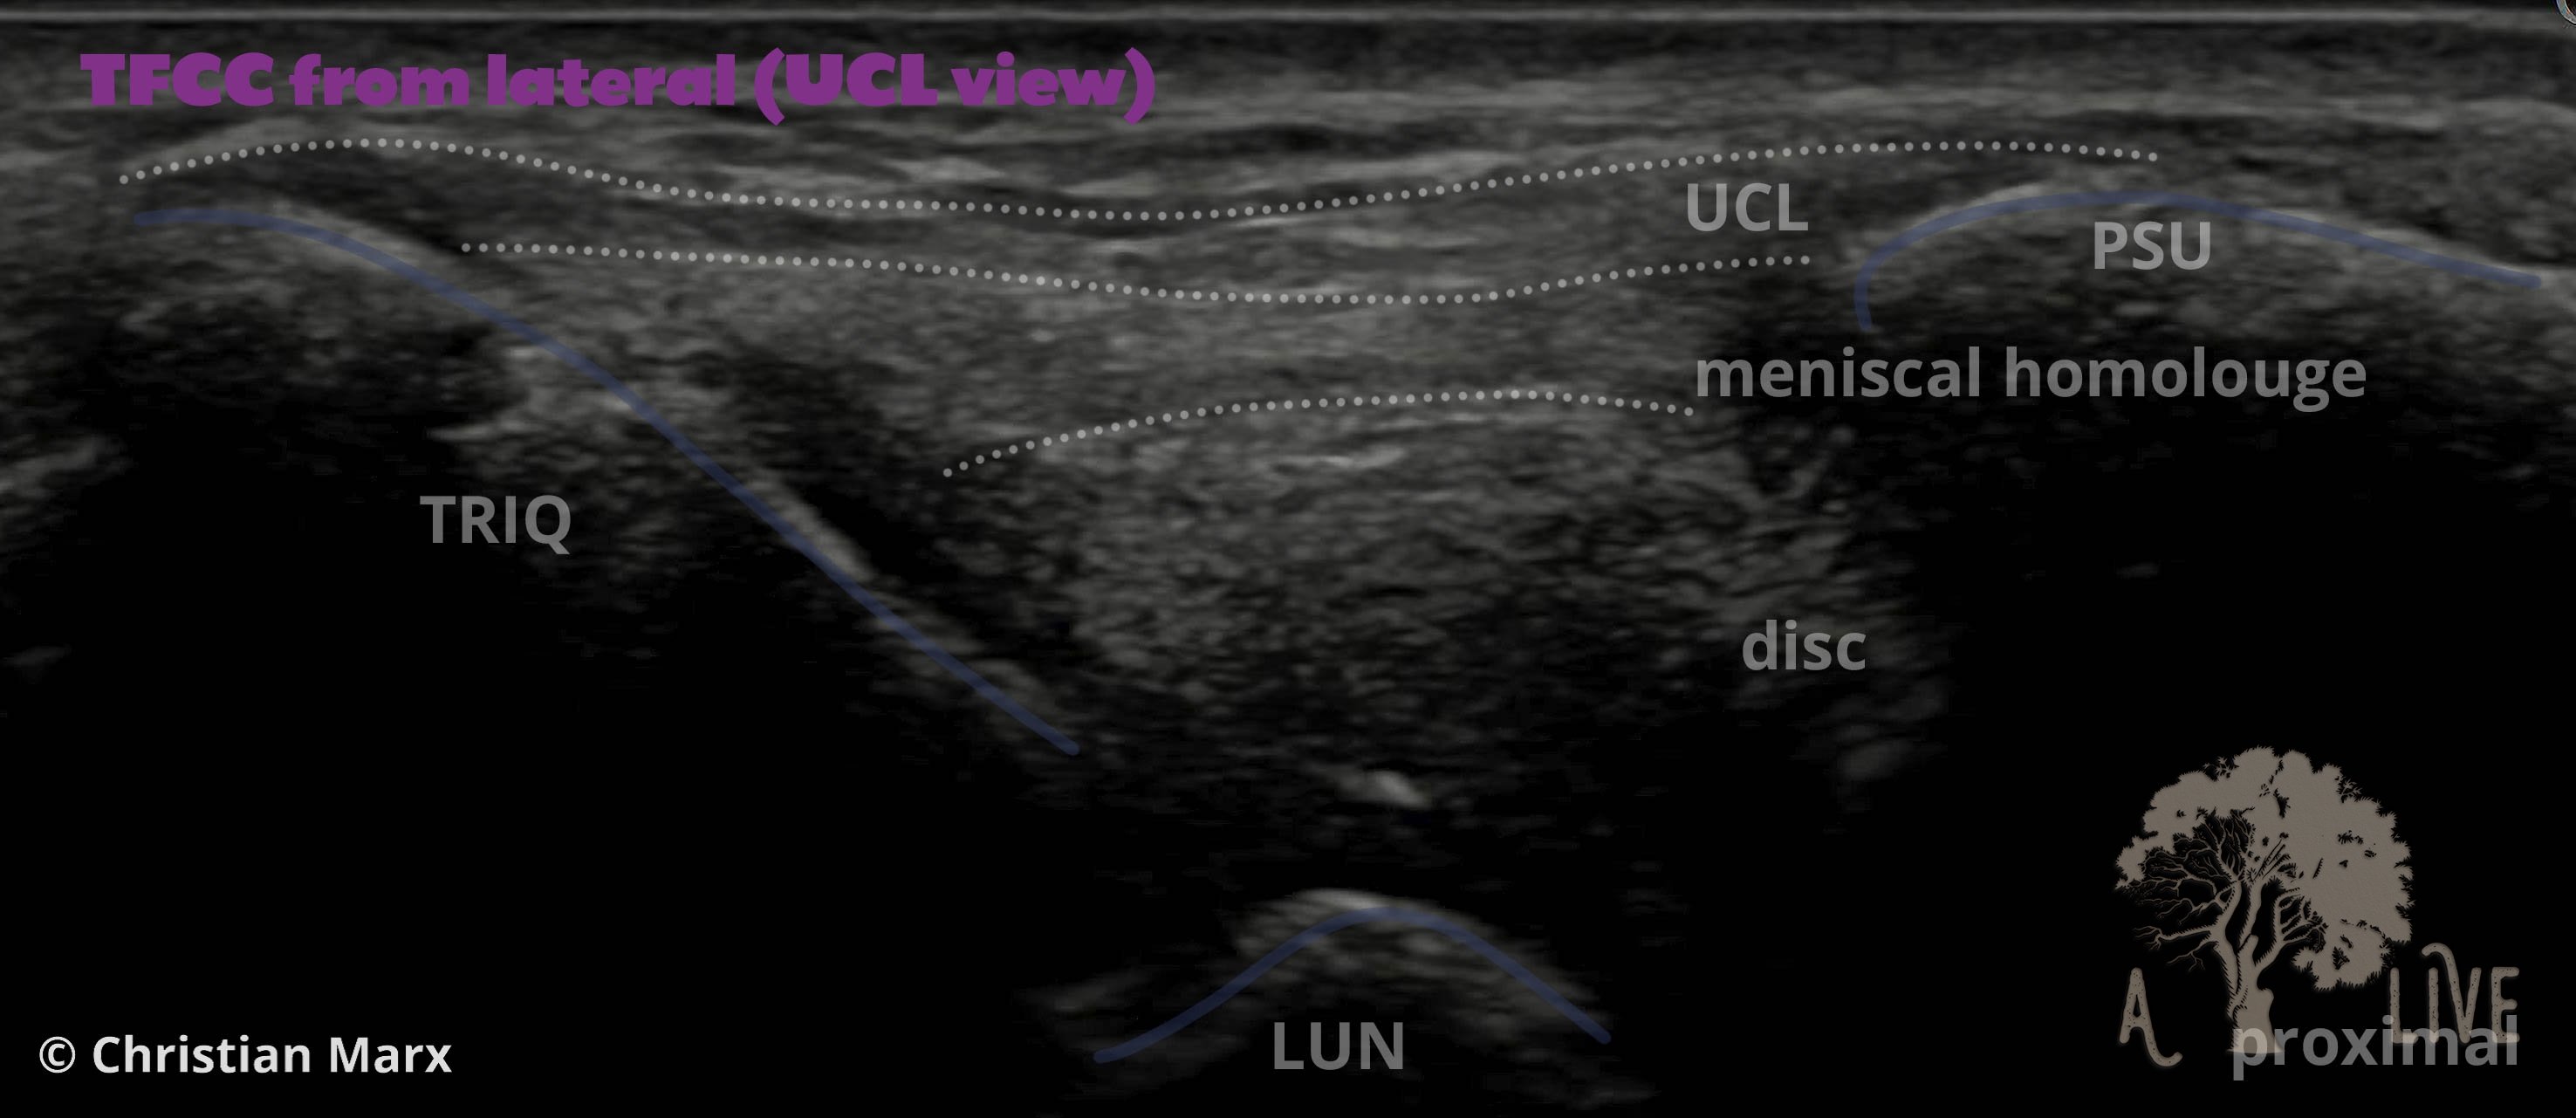

carpal ligaments